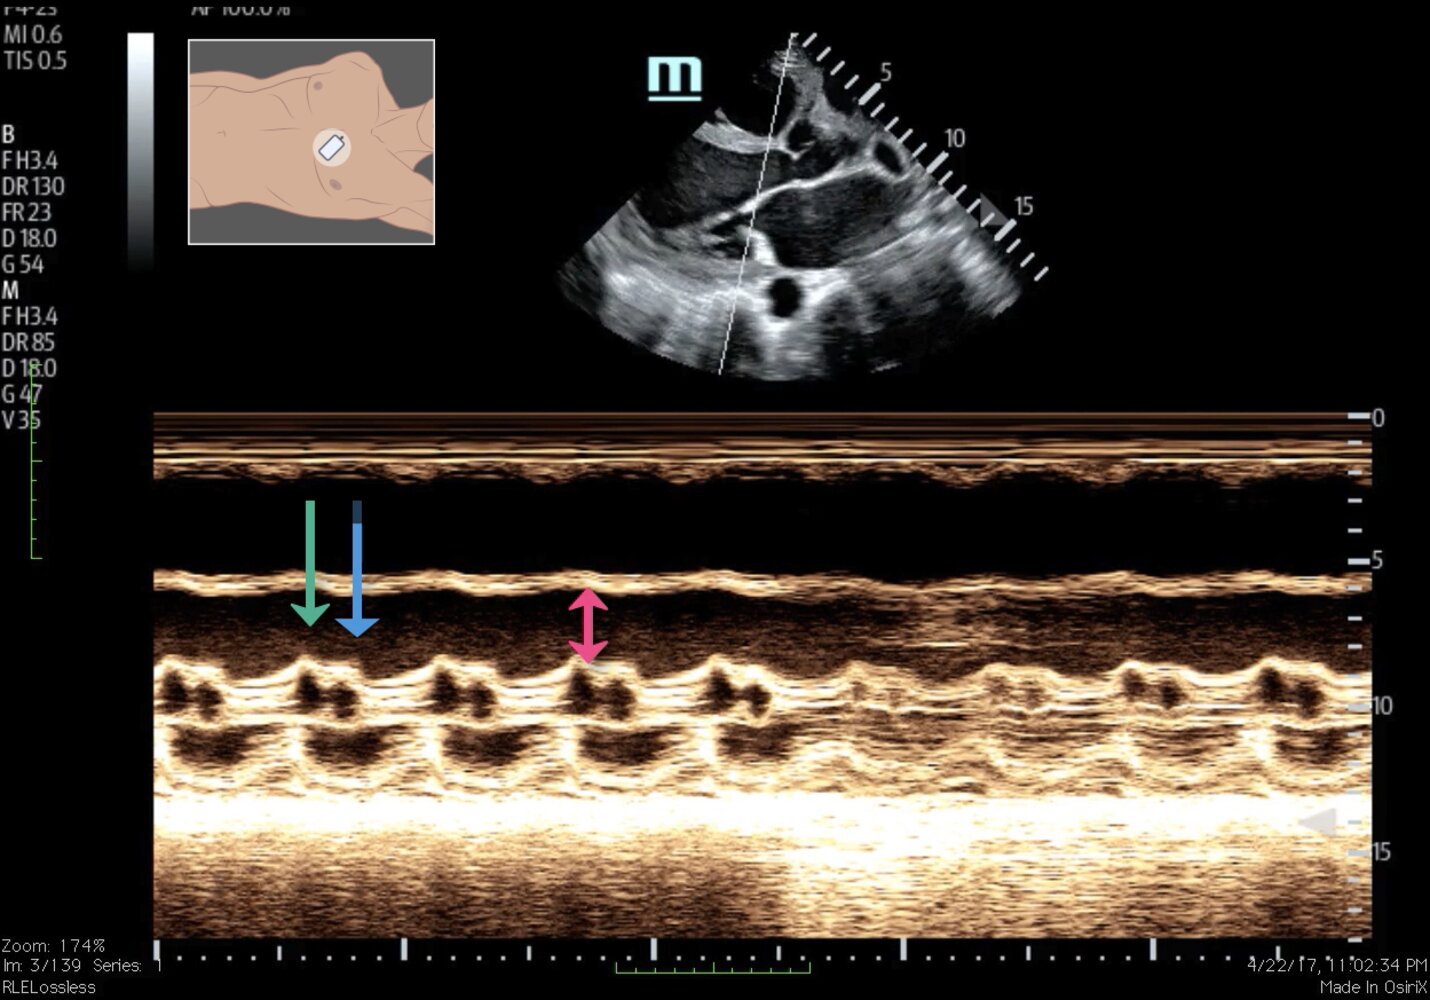

Transthoracic echocardiogram (TTE) [7][24]

- Indications: all patients with suspected acute heart failure (imaging modality of choice) [25]

-

Characteristic echocardiographic findings of AHF

- Reduced or normal LVEF [26]

- Diastolic dysfunction

- Left atrial dilation, valvular disorders [24]

- Pericardial effusion

- Right ventricular systolic dysfunction, increase in right ventricular systolic pressure

Specific findings related to underlying etiology

- Acute myocardial ischemia: regional wall motion abnormalities, papillary muscle rupture, mitral valve regurgitation, septal or ventricular free wall rupture [25]

- Endocarditis: vegetation on the valve